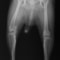

■ 症例24 キャバリア 7か月

左右膝蓋骨内方脱臼(左:グレードⅣ 右:グレードⅢ)

以前から左右後肢の跛行が認められ、整形外科学的検査・レントゲン検査により左右の膝蓋骨脱臼が認められた。症状が重度である左膝の膝蓋骨脱臼整復術を行った。外科手技は縫工筋及び内側広筋の解放、脛骨粗面の外側転位、滑車ブロック形造溝術、内外側関節方の縫縮を実施した。術後一か月時点で、左の膝蓋骨は安定しており経過は良好である。

本症例は成長期における重度の膝蓋骨脱臼であり、術後の再発の可能性もあるため、経過をしっかりと観察していく必要がある。また、今回手術を実施していない右膝に関しても経過を観察し、手術を検討していくこととする。